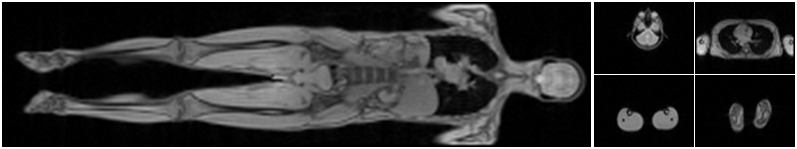

Refer to caption

Figure 3: Left: Coronal plane of MRI scan showing the entire patient. Right: Axial slices on which manifold learning is performed.

We run experiments on 13 whole body scans, such as the example shown in Fig. 3. A medical expert assigned an anatomical label (head, neck, lung, abdomen, upper leg, and lower leg) to each of the axial slices (64×\times64 pixels). We apply Laplacian eigenmaps to embed the high dimensional slices in a two-dimensional space; we use a 40-nearest-neighbor graph with a heat kernel of temperature t=49𝑡49t=49. To predict the anatomical label of an axial image, we perform nearest-neighbor classification in the learned low-dimensional space. We repeat this classification procedure for different values of error tolerance ε𝜀\varepsilon ranging from 1×1041superscript1041\times 10^{-4} to 5×1045superscript1045\times 10^{-4}.